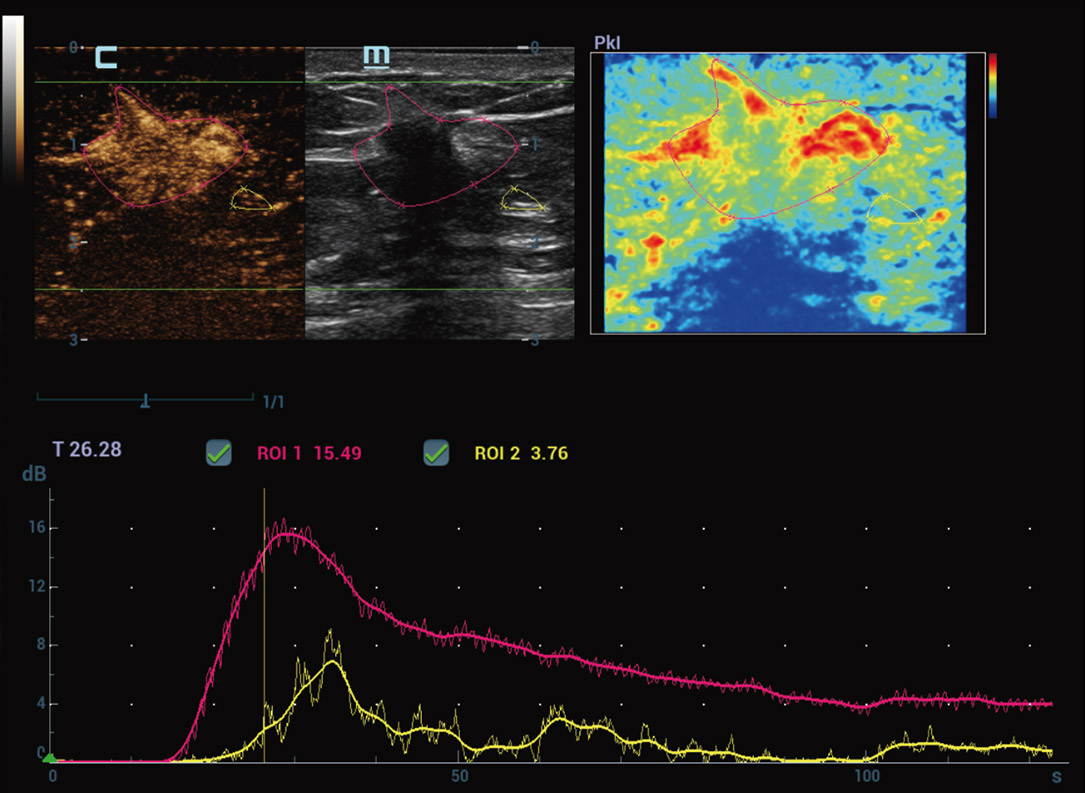

Nieuwe CEUS-kwantificatieanalyse

Nieuwe CEUS QA Borst kwaadaardig

De tijd-intensiteitscurve maakt kwantitatieve analyse van CEUS-beeldvorming mogelijk. De nieuwe CEUS QA biedt tools voor geavanceerde kwantitatieve analyse die ondersteuning bieden bij tumorbeoordelingen en klinisch onderzoek.